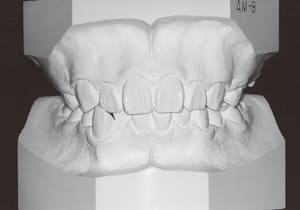

1 Initial Visit 2-11-’88

3 Initial Visit 2-11-’88

4 Initial Visit 2-11-’88

The Class II condition is pronounced, with a significant overjet of 12.5 mm(3). Although the teeth size are large, crowding is relatively mild. The maxillofacial structure has good depth and a robust bone framework(5). The mandible itself is solid , robust gonial angle, but there is significant anterior-posterior displacement relative to the maxilla(ANB 10.0°). While there is no confirmed history of thumb-sucking or similar habits, the lower lip is already pushing up against the maxillary incisors. The cause of this condition is unknown.